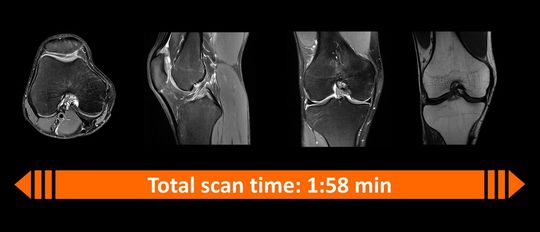

Die Kombination aus Deep Resolve und der Simultaneous-Multi-Slice-Technologie ermöglicht es, das gesamte Knie in zwei Minuten zu scannen.(Bild:  Siemens Healthineers)

Die Kombination aus Deep Resolve und der Simultaneous-Multi-Slice-Technologie ermöglicht es, das gesamte Knie in zwei Minuten zu scannen.

(Bild: Siemens Healthineers)

Die Verkürzung der Scanzeit ist besonders vorteilhaft für Patienten, die sich im MRT-Scanner unwohl fühlen, beispielsweise Kinder oder Menschen die an Klaustrophobie leiden. Das frühe Nutzen aller verfügbaren Rohdaten hilft, die Dauer der Scans zu verkürzen. Damit können die Deep-Resolve-Algorithmen die Scanzeiten um bis zu 70 Prozent beschleunigen und gleichzeitig die Auflösung verdoppeln. Durch die Simultaneous-Multi-Slice (SMS)-Technologie von Siemens Healthineers kann die Scanzeit noch weiter beschleunigt werden – um bis zu 80 Prozent.